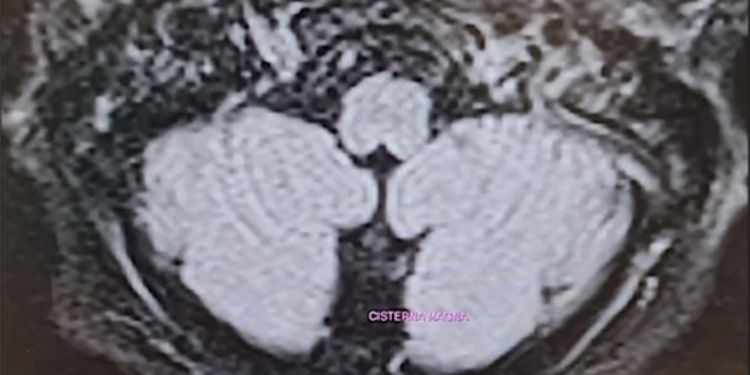

Acute Hypomagnesemia-Induced Cerebellar Down-Beat Nystagmus Syndrome Due to Benign Paroxysmal Positional Vertigo: A Case Report

Authors: Marcelli Vincenzo, Giannoni Beatrice, Marcelli Edoardo, Volpe Giampiero, Faralli Mario, Rita Fetoni Anna, Enrico Pettorossi Vito

DOI: 10.14302/issn.2470-5020.jnrt-24-5148